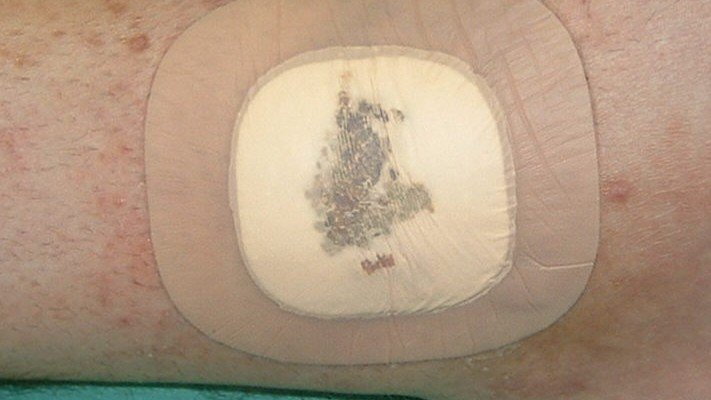

Polyurethan-Schaumverbände -mit Silikonbeschichtung- antiinfektiös

Zusätzliche Fotos ![]() 2

2